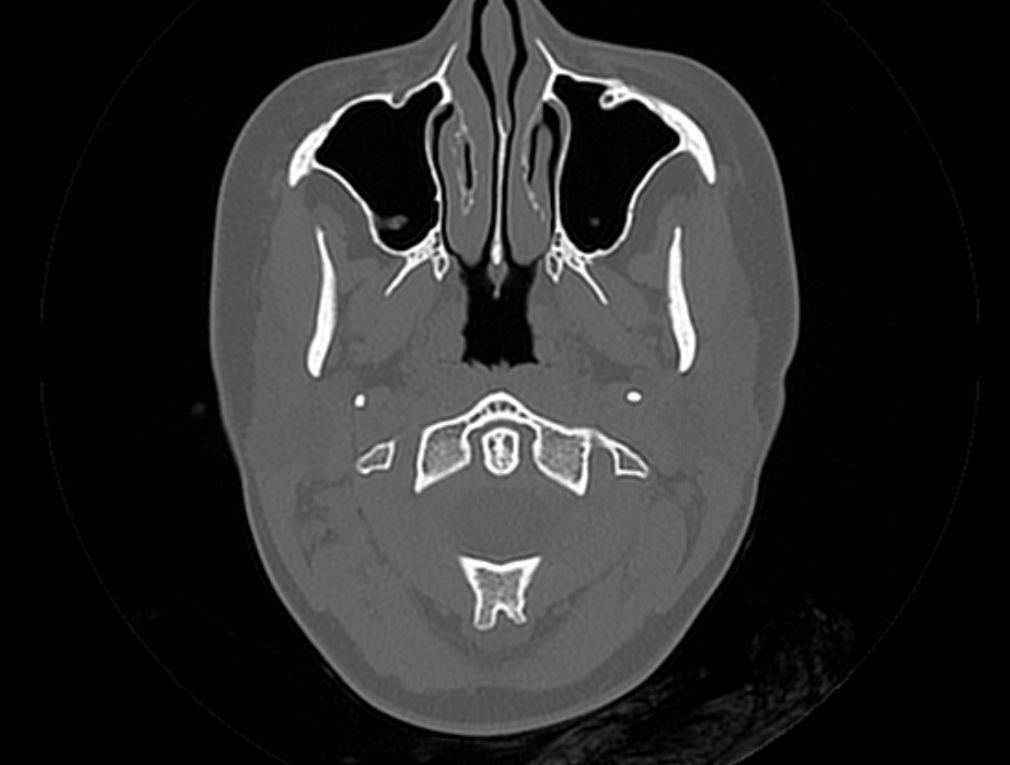

Мультиспиральная компьютерная томография является наилучшим методом диагностики патологии костей черепа. В основе методики лежит использование рентгеновского излучения с последующей цифровой обработкой полученных данных и получения трехмерных реконструкций изображений.

Костная ткань отличается высокой плотностью и способна в большой степени поглощать рентгеновские лучи. Поэтому на послойных снимках, полученных при проведении мультиспиральной КТ черепа можно детально рассмотреть свод черепа, кости лица, основание черепа. Это позволяет с наибольшей точностью визуализировать различные объемные образования, такие как остеомы, дифференцировать фиброзную дисплазию или костные метастазы. Преимуществами методики КТ является отличная визуализация костных структур, быстрота выполнения процедуры и доступная цена. Все это делает КТ незаменимой при диагностике травматических повреждений (например переломов основания черепа или орбит), аномалий развития, при планировании оперативных вмешательств.

Что показывает КТ черепа

- наличие чужеродных предметов;

- скрытые переломы;

- смещение костей;

- опухоли как доброкачественные, так и злокачественные

- нарушенное кровообращение;

- воспалительные заболевания

- метастазы и их локализацию